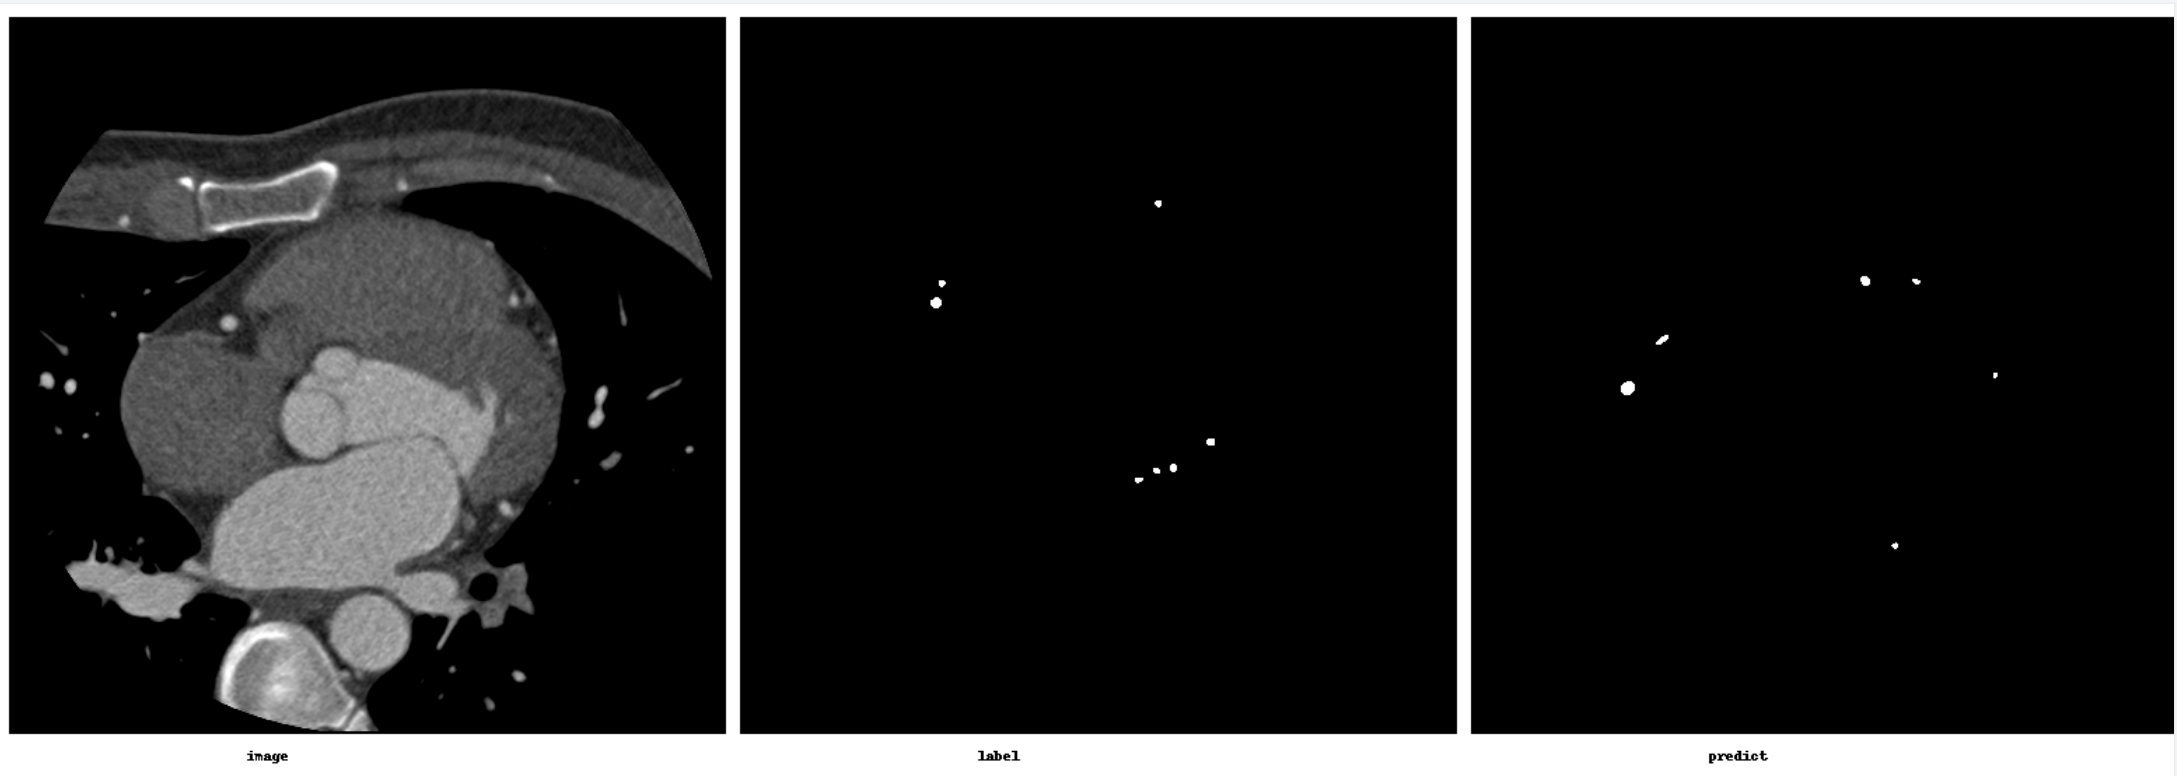

3.模型测试

评价指标:

HD95: 5.20

Average Dice: 0.8144